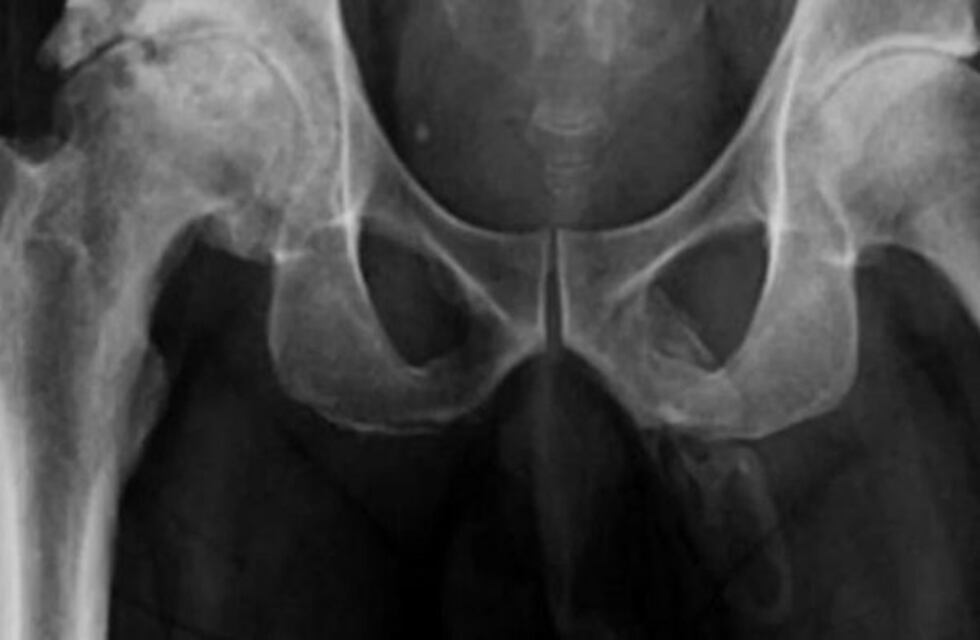

El paciente se había caído mientras caminaba con su bastón, por lo que acudió al Hospital Lincoln con un fuerte dolor en una de sus rodillas. Al practicarle un examen de rayos X en la zona de la cadera, los médicos advirtieron algo inusual: una extensa calcificación de los tejidos blandos que forman el pene.

Esta condición se denomina osificación del pene. Al ser consultado por los profesionales, el hombre afirmó tener molestias pero no tenía otros síntomas que delataran problemas urológicos.